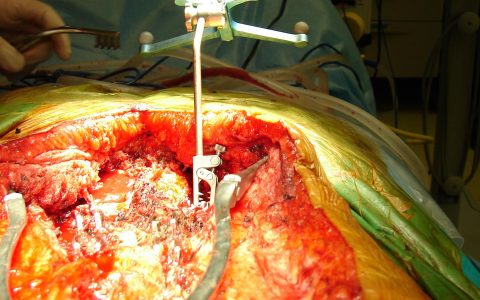

Περίπτωση Πα. Γι.: Επανεγχείρηση σκολίωσης ενηλίκων

Η κα Πα.Γι. 61 ετών, έπασχε από σκολίωση της σπονδυλικής στήλης από νεαρή ηλικία. Σε ηλικία περίπου 40 ετών άρχισε να παραπονιέται για πόνο στην οσφυϊκή μοίρα της σπονδυλικής στήλης. Η αντιμετώπιση του πόνου ήταν συντηρητική. Προοδευτικά ο πόνος επιδεινώθηκε παρά την αγωγή, γι’ αυτό αναζήτησε περαιτέρω θεραπευτική αντιμετώπιση. Εικ 1: Προεχειρητικές ακτινογραφίες της σπονδυλικής